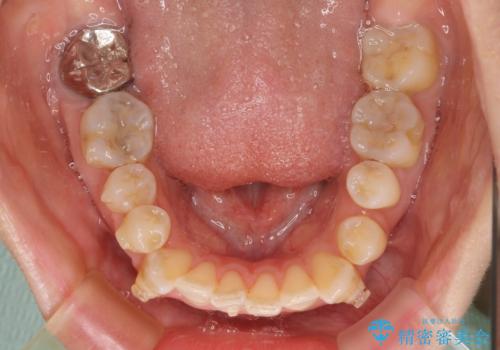

八重歯と開咬の抜歯矯正 ワイヤー装置を併用したインビザライン矯正治療

- 咬み合わない前歯と八重歯などのデコボコを気にして来院された患者様です。

上下前歯の位置を比較すると上顎が前方にあり、デコボコ改善でより上顎が前方に行く可能性があります。

開咬の改善にはインビザラインが有効であり、インビザライン単体での治療を検討しましたが、上顎前突を回避するために上顎左側第一小臼歯抜歯を行うこととしたため、補助装置とワイヤー矯正を併用した上で、インビザラインによる矯正治療を行うこととしました。

インビザライン矯正治療では、臼歯の圧下による前歯部の早期接触が大きな問題となっています。開咬では、その臼歯圧下を逆手にとって前歯部の非接触を改善させることができます。